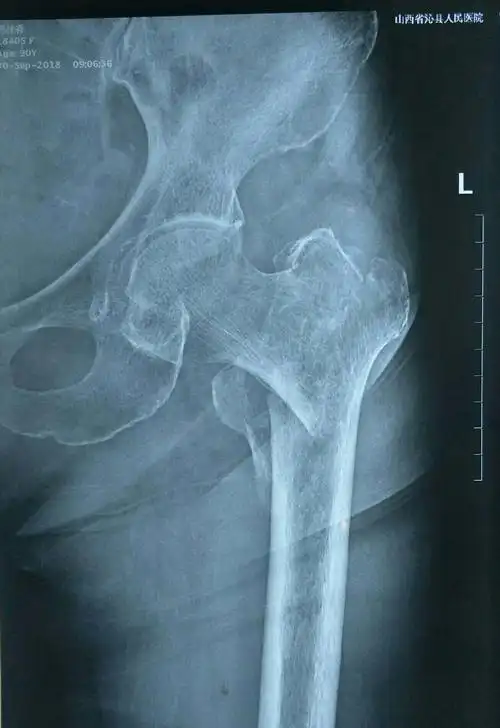

左侧股骨粗隆间骨折(改良evens三型) - 美篇

诊断证明书显示,临床诊断结果为闭合性颅脑损伤中型,包括左侧额部创伤